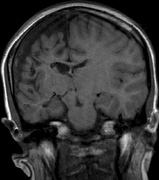

Mental retardation and seizures in TSC are often associated with benign CNS astrocytic hamartomas.131 On imaging, the cerebral lesions show three patterns:132

1. Superficial cortical sclerosis (parenchymal hamartoma) which distort the gyri. Microscopy shows large atypical fibrillary type astrocytes with few associated neurons and areas of calcification.133 The numerous abnormal glial processes and fibers make the tissue abnormally firm or “sclerotic” on palpation (Fig. 13).132

2. Subependymal nodules (SEN) are typically found along the lateral borders of the ventricles and parehncymal brain lesion (“cortical tubers”) (Figs. 14 and 15). Calcification in the first year of life is rare.132

On MRI imaging, the subependymal nodules and parenchymal brain lesions of infants (age ≤3 months) and adults show different signal characteristics. Infant CNS tubers are hyperintense on T1-weighted images and hypointense on T2-weighted images, which is the opposite of the pattern seen in adults.134 Malignant transformation of SEN occurs in about 10% to 15% of patients and the resultant subependymal giant cell astrocytoma accounts for 25% of premature deaths in TSC.135,136

Fig. 13. Tuberous Sclerosis Complex: “cortical sclerosis.” Numerous abnormal glial processes make the tissue abnormally firm or “sclerotic” on palpation.132

Fig. 14. Tuberous Sclerosis Complex: Sub-Ependymal nodules. These are typically found along the lateral borders of the ventricles.132

Fig. 15. Tuberous Sclerosis Complex. (a) Patient 1: Axial CT scans demonstrating typical calcification of subependymal nodules in a 13-year-old girl with a history of seizures. (b and c) Patient 2. (b) Axial T2-weighted images demonstrate calcified subependymal nodules (arrowheads) and cortical tubers typical of tuberous sclerosis. (c) Widespread cortical tubers are seen on a coronal FLAIR sequence as thickening of the cortex and high signal of the subcortical white matter.